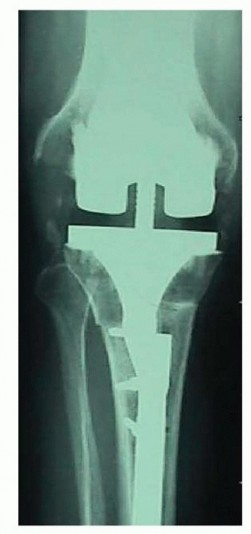

Following debridement, the tibial bone defects are formally assessed and classified according to the Anderson Orthopaedic Research Institute criteria. The intramedullary canal of the tibia is sequentially reamed to determine the appropriate diameter and length of the diaphyseal stem required to bypass the metaphyseal defects and achieve stable cortical engagement in Zone 3.

Zonal Fixation and Stem Implantation

Regardless of the grafting technique utilized, the definitive implant must achieve rigid stability. Diaphyseal engaging stems are mandatory when massive bone grafting is performed. The stem must bypass the grafted area by a minimum of two cortical diameters into the intact diaphysis.

Cementless, fluted, tapered stems are widely favored as they provide excellent rotational stability and immediate rigid fixation in the diaphysis. The metaphyseal portion of the implant, resting on the bone graft, is typically cemented. Care must be taken to prevent cement extrusion between the structural allograft and the host bone interface, as this will mechanically block biological incorporation and lead to graft nonunion. Offset stems may be required to accommodate the mismatch between the center of the diaphyseal canal and the center of the tibial plateau, ensuring optimal coverage of the reconstructed metaphysis.